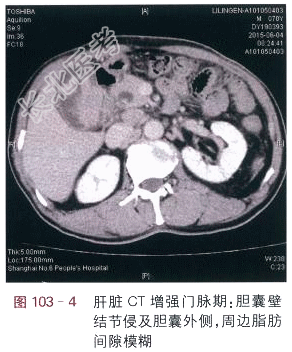

读片分析:肝脏CT平扫:胆囊内见多个结石,胆囊壁内侧呈局限性增厚,形态不规则(见图103-1),肝脏CT增强扫描动脉期:胆囊壁结节呈明显强化,结节呈分叶状,并侵及胆囊壁外侧(见图103-2),门脉期、延时期:胆囊壁结节侵及胆囊外侧,周边脂肪间隙模糊(见图103-3)。